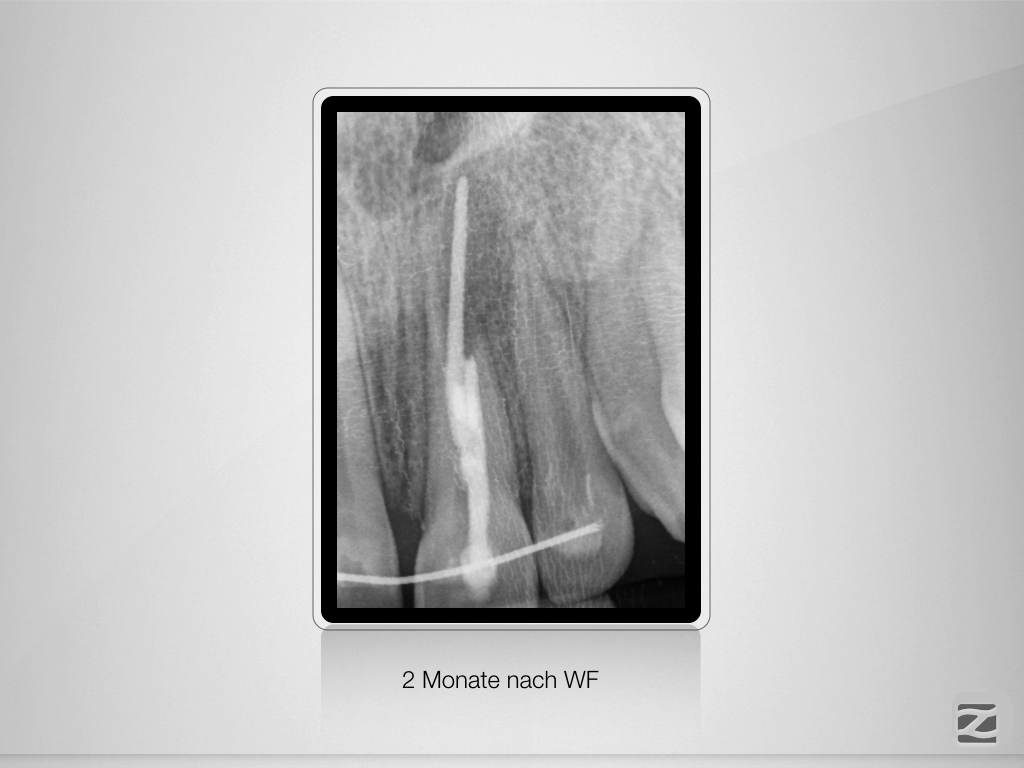

Traumspätfolge